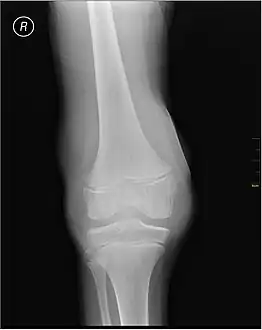

Synovial Fluid analysis is another method to diagnose Hemarthrosis. It involves a small needle being inserted into the joint to draw the fluid.[8] Reddish-colored hue of the sample is an indication of the blood being present. Imaging tests are normally done. The tests also include MRI, Ultrasound and X-ray test, which give better information about the joint inflammation.[9]